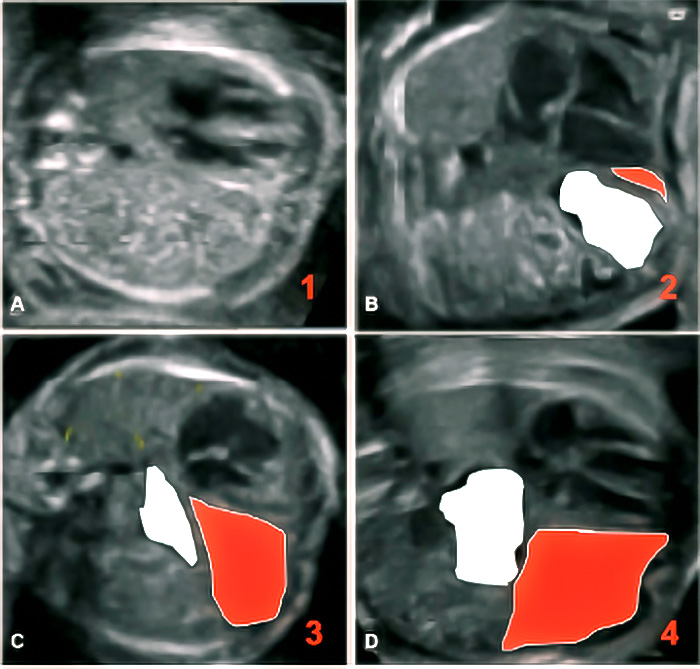

24 : Que représente cette série d’images en coupes axiales fœtales ?

1. A) Une séquence d’imagerie de l’abdomen fœtal

B) Une évolution progressive d’une hernie diaphragmatique congénitale (HDC)

C) Une classification des degrés de sévérité de l’HDC

D) Une comparaison entre une IRM fœtale et une échographie standard

E) Une analyse Doppler des flux sanguins pulmonaires

Réponse(s) correcte(s) :

• B) Une évolution progressive d’une hernie diaphragmatique congénitale (HDC)

• C) Une classification des degrés de sévérité de l’HDC

Explication : Cette figure illustre différents stades ou degrés d’engagement des organes abdominaux dans le thorax fœtal, caractéristiques d’une HDC.

25 : Quelles structures sont mises en évidence par les couleurs sur ces images ?

1. A) Le foie en position intra-thoracique

B) Les poumons fœtaux

C) L’intestin hernié

D) Le diaphragme en position normale

E) Le liquide amniotique

• A) Le foie en position intra-thoracique

• C) L’intestin hernié

Explication : La coloration met en évidence les organes abdominaux déplacés dans le thorax, notamment le foie (en rouge) et l’intestin (en blanc), qui sont des marqueurs de sévérité de l’HDC.

26 : Quels critères permettent d’évaluer la sévérité de l’HDC ?

1. A) Le volume pulmonaire résiduel

B) La position du foie (intra-thoracique ou non)

C) Le Lung-to-Head Ratio (LHR)

D) L’épaisseur du diaphragme

E) La présence d’un hydramnios

• A) Le volume pulmonaire résiduel

• B) La position du foie (intra-thoracique ou non)

• C) Le Lung-to-Head Ratio (LHR)

Explication : La sévérité de l’HDC est déterminée par le volume pulmonaire restant, la herniation hépatique et le LHR, qui prédit le risque d’hypoplasie pulmonaire.

27 : Quelle est la valeur pronostique d’une herniation hépatique dans l’HDC ?

1. A) Elle est associée à une hypoplasie pulmonaire plus sévère

B) Elle n’a pas d’impact sur le pronostic

C) Elle est associée à un meilleur taux de survie néonatale

D) Elle constitue une indication possible pour une occlusion trachéale fœtoscopique (FETO)

E) Elle entraîne une insuffisance hépatique fœtale

• A) Elle est associée à une hypoplasie pulmonaire plus sévère

• D) Elle constitue une indication possible pour une occlusion trachéale fœtoscopique (FETO)

Explication : La herniation hépatique est un facteur de mauvais pronostic, car elle réduit le volume pulmonaire fonctionnel. Dans certains cas, une intervention FETO peut être envisagée pour améliorer le développement pulmonaire in utero.